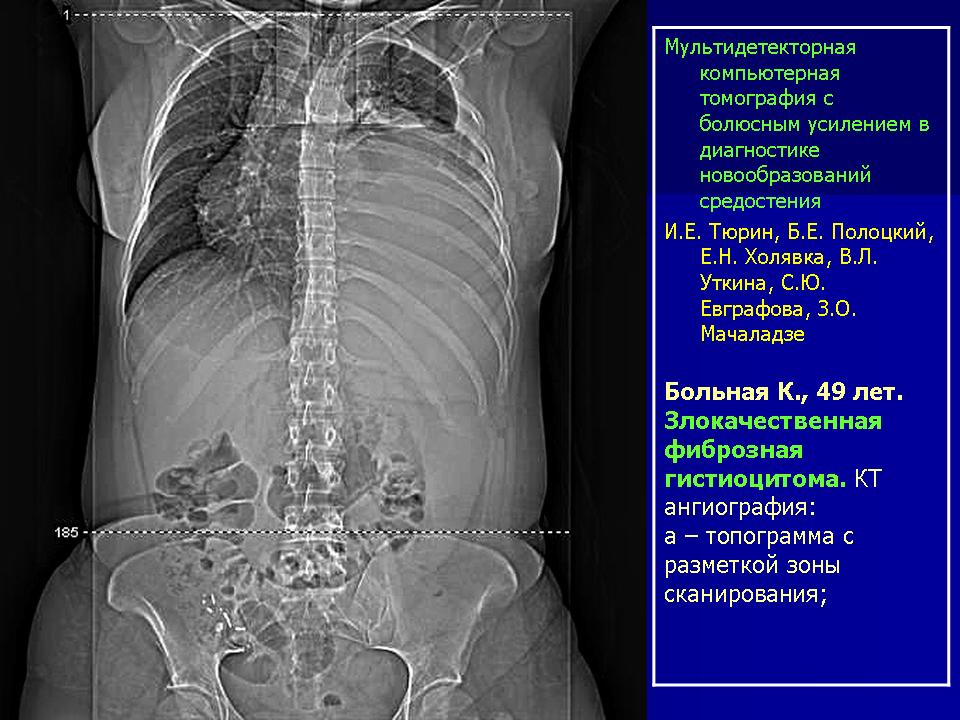

Средостение.  "Опухолевый рост".

Продолжение.